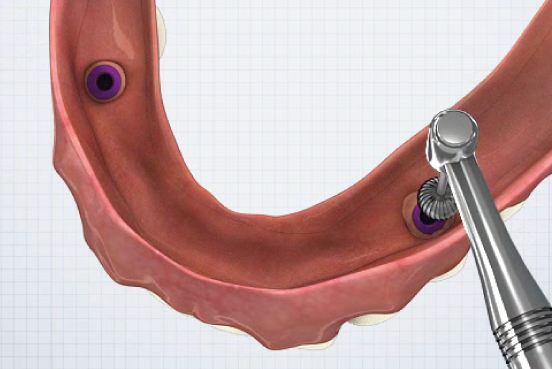

Direct Technique

①

- Healing Abutment 제거- Plastic Carrier을 이용하여 EZ LOCK Abutment 체결

▼

②

- EZ LOCK 전용드라이버를 이용하여 EZ LOCK 체결 (25N~)▼